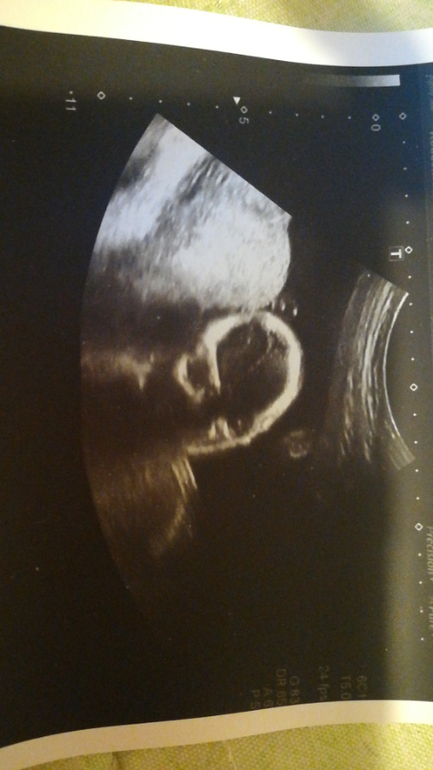

УЗИ, КТГ, доплерВчера был долгожданный 2й скрининг. Урвала пару фоточек на память

По части развития малыша все хорошо.